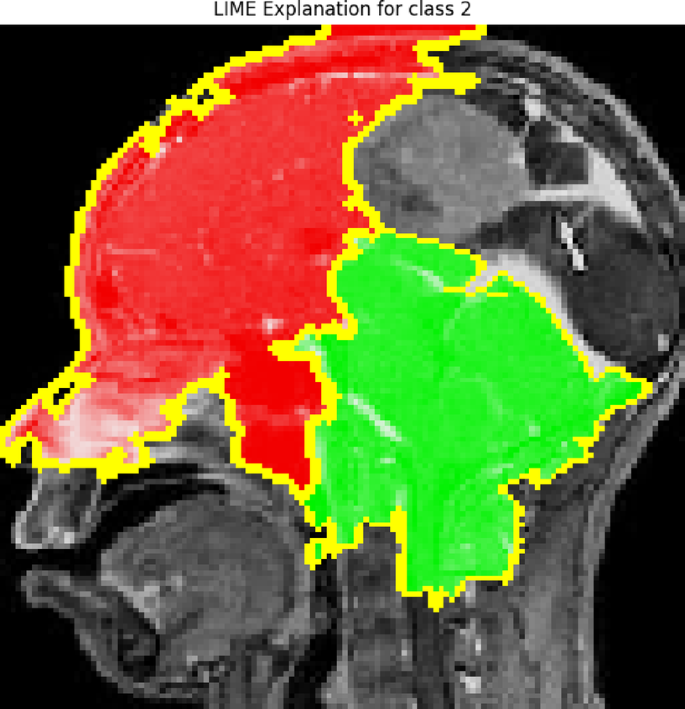

LIME

LIME is a method to interpret black-box models by fitting a linear model locally in the space around the prediction. LIME modifies a small portion of the input and analyzes how the output changes; after doing so, a simpler, easier-to-understand model (for example, a linear model) is trained to mimic the ML model in the locally neighboring area of the modified ML.

The explanation model g is selected to minimize:

Where L(f, g, πx) measures the fidelity between the complex model f and the interpretable model g in the local neighborhood of the instance x, and Ω(g) is a regularization term to ensure simplicity37,38.

The technique outlined in this work, called Guided Grad-CAM, merges the benefits of guided backpropagation and Grad-CAM to give a full image of the locations leading to the model’s prediction. The overlay in Fig. 21 shows the specific locations in the brain MRI image that the model is concentrating on, particularly the area surrounding the tumor. The areas receiving the greatest focal point from the model are represented by patches of green and blue, and the overlay demonstrates how these areas impact the decision class. This method provides a more complete and accurate explanation for why a model is seeing what it sees to ensure that the model’s focal point is clinically aligned. In this study, LIME is used to identify the decision boundaries of the ensemble model as further evidence of the ways these different features drive one classification decision to the next. In Fig. 22, using LIME, this study provides an interpretable explanation for the model’s prediction of class 2. The red and green markings highlight which parts of the MRI image contributed most to the classification decision. Certain red sections are damaging to the prediction, while the green sections pose a positive increase to the prediction. As a byproduct of perturbing the original image and then testing how those perturbed images change the model’s decision, LIME enables, even approximates identification of the decision boundary by providing explanations of why this model predicted that class. This kind of openness gives physicians the ability to evaluate whether the model’s prediction is consistent or reasonable with medical expertise.

LIMA XAI heatmap.